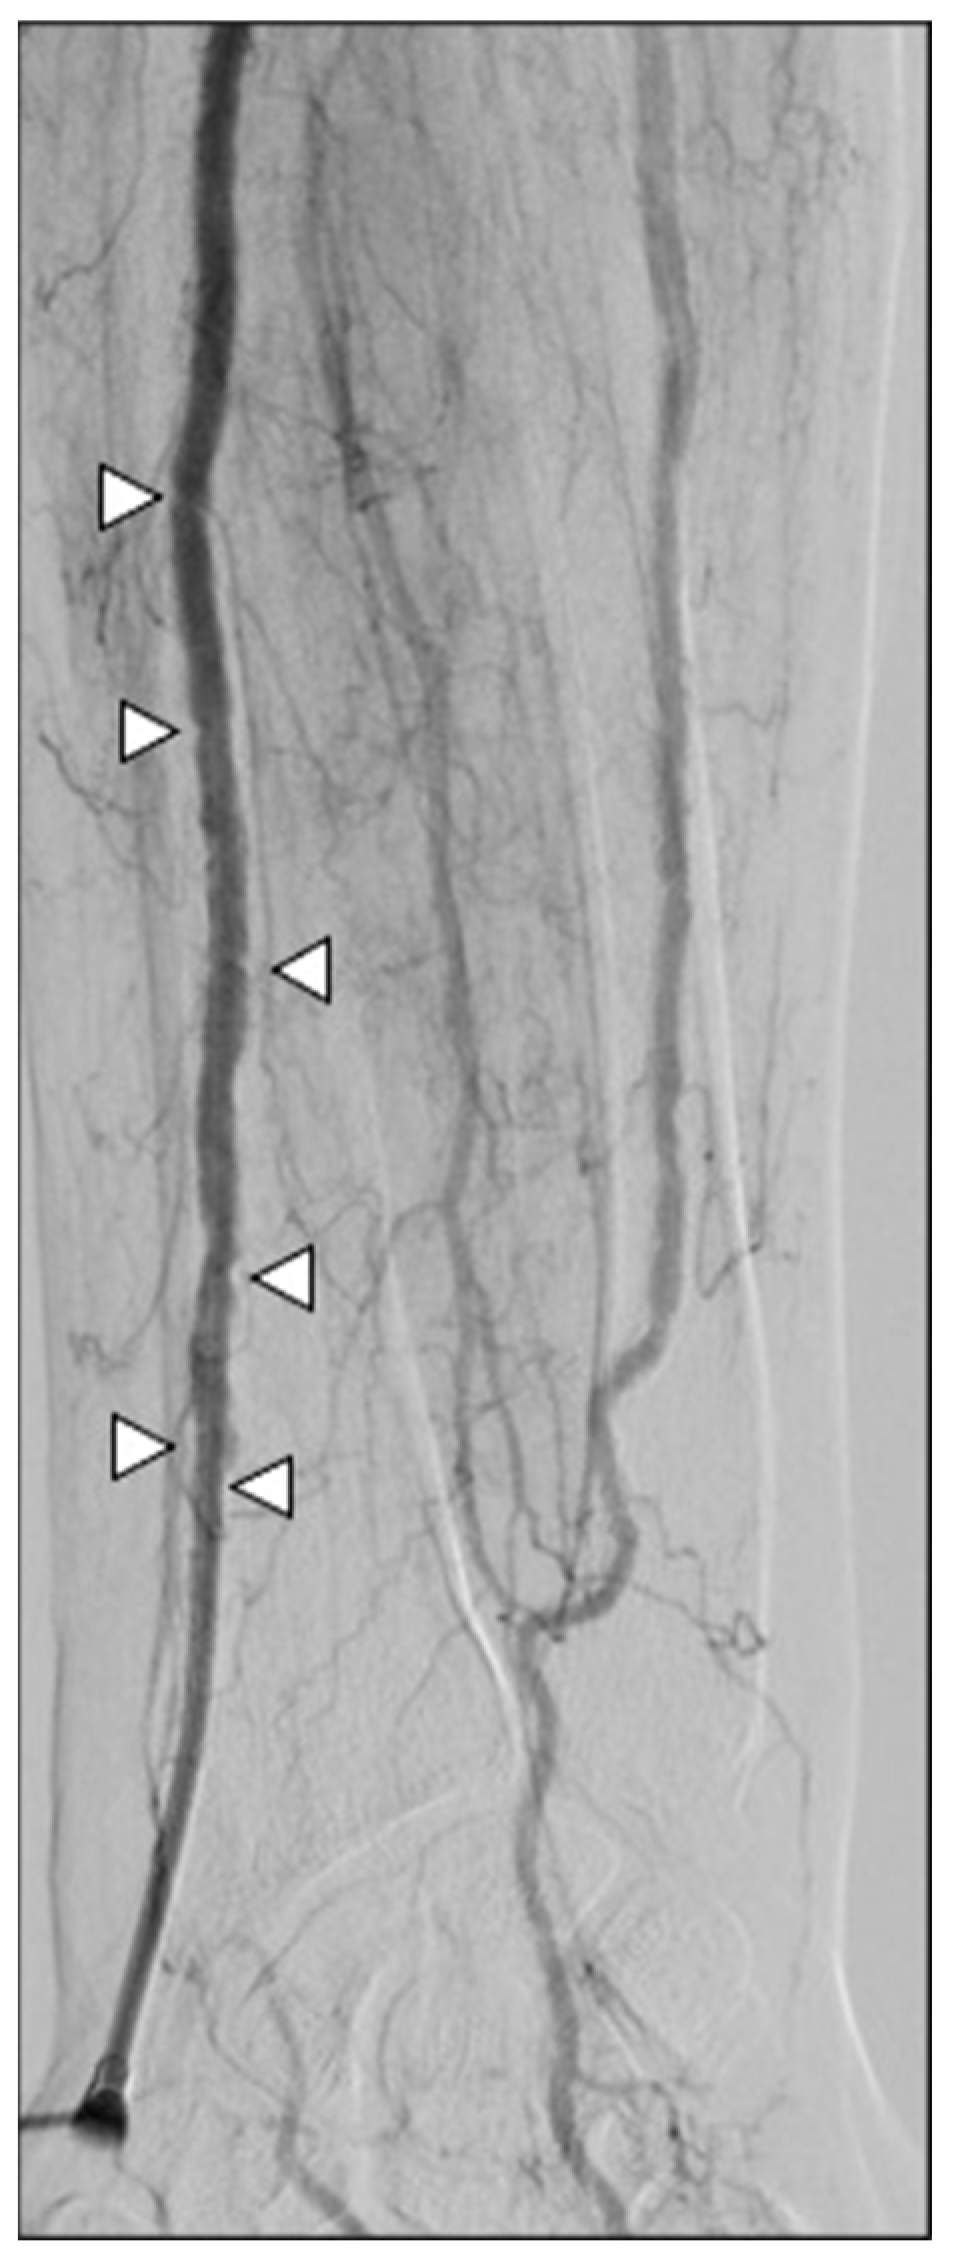

- Iezzi, R.; Posa, A.; Contegiacomo, A.; Maresca, A.; Rodolfino, E.; Merlino, B.; Bilhim, T.; Guimaraes, M. Application and Validation of a transRADial Access Score (RAD-Access) in Patient Selection for Safe Radial Access in Liver Cancer Intra-Arterial Procedures. Cancers 2025, 17, 1385. [Google Scholar] [CrossRef]